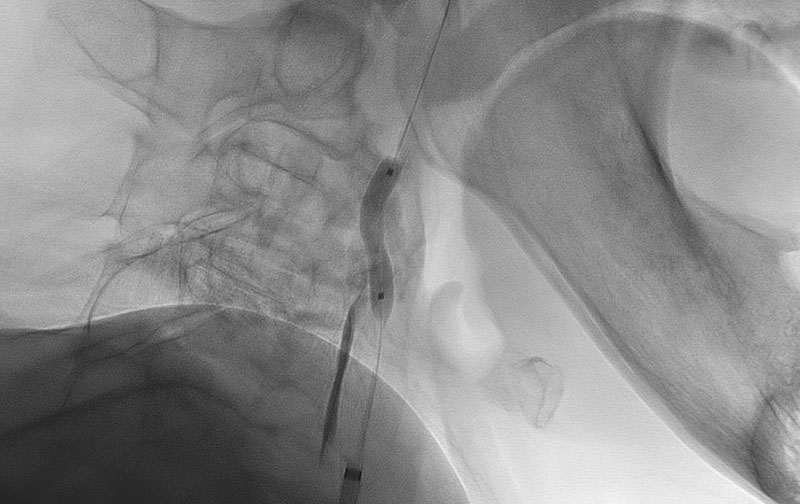

No.1113 手術中